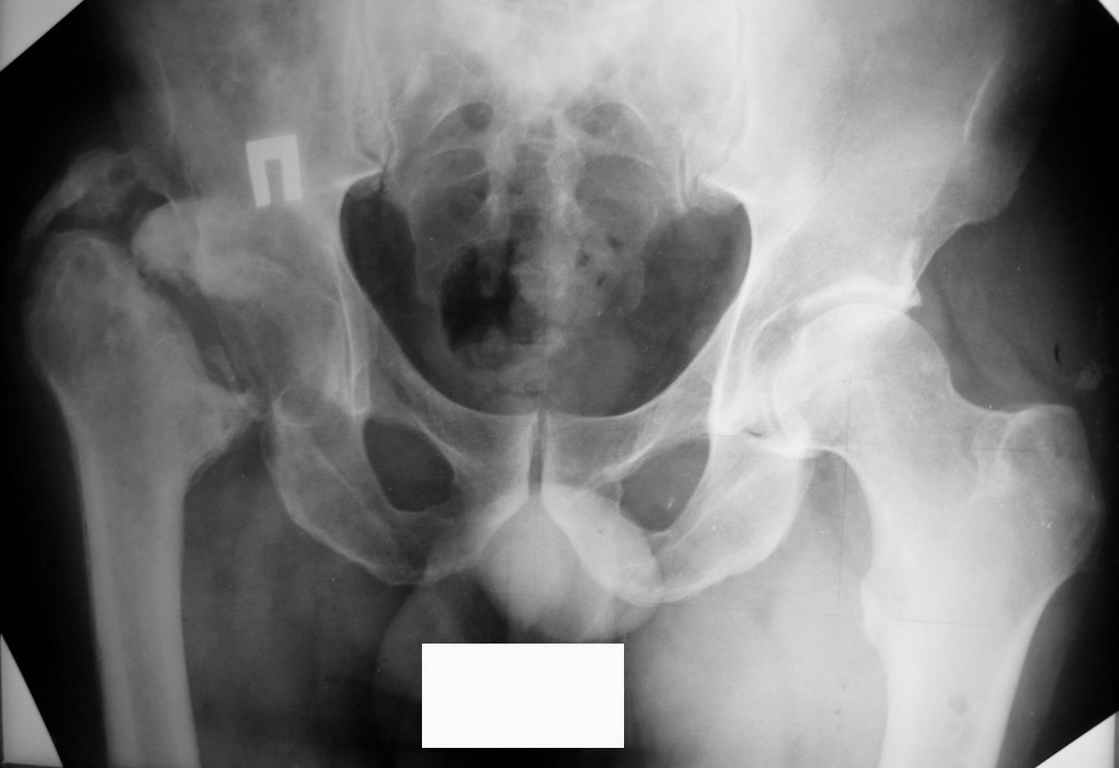

Был оперирован, среди прочего - остеосинтез DHS-фиксатором чреcшеечного перелома правого бедра, DCS-фиксатором остеосинтез оскольчатого чрезмыщелкового перелома левого бедра. Однако, в связи с развитием гнойного коксита были вынуждены убрать DHS-фиксатор и головку. Гнойный свищ правого тазобедренного сустава закрылся сразу после операции. Из-за вторичного смещения и поломки винтов пришлось удалить DCS-фиксатор и сращивать левое бедро внешней иммобилизацией. Прошло чуть более года. Пациент ходит с опорой на обе ноги,пользуется палочкой. Справа относительное укорочение 3см. Слева варус 33гр., тугой ложный сустав н/3бедра. Движения в коленных суставах почти в полном объёме.Перед нами встали вопросы, с чего начать? Протезирование правого ТБС? Восстановление опорности левой конечности? Воспользоваться-ли для этого интрамдулярным остеосинтезом гвоздём с блокированием с ретроградным введением? Стараться при этом восстановить полностью длину, или оставить на потом, на аппаратное решение? Или сразу попытаться использовать аппарат Илизарова? Но боимся потерять колено? Вопросов много.С благодарностью выслушаем все мнения.Заранее спасибоРахматуллин Ринат НургаяновичГКБ N 13 г.Уфа.

Эндопротезирование правого тазобедренного сустава в условиях бывшего инфицирования рискованно, весьма вероятно нагноение эндопротеза. По моему мнению следует произвести корригирующую вальгизирующую остеотомию на высоте деформации ложного сустава левой бедренной кости с иссечением небольшого клина с основанием обращенным медиально (через зону ложного сустава без предварительного разделения костных фрагментов)и медиализацией диафиза бедра. Фиксация или пластиной с клинком на 95 градусов, или фиксатором типа DF - LCP. Доступ лучше расширенный с отсечением бугристости большеберцовой кости в месте прикрепления собственной связки надколенника и ее последующая рефиксация. После сращения решать вопрос о возможности удлинения правой голени в аппарате Илизарова для компенсации укорочения конечности.